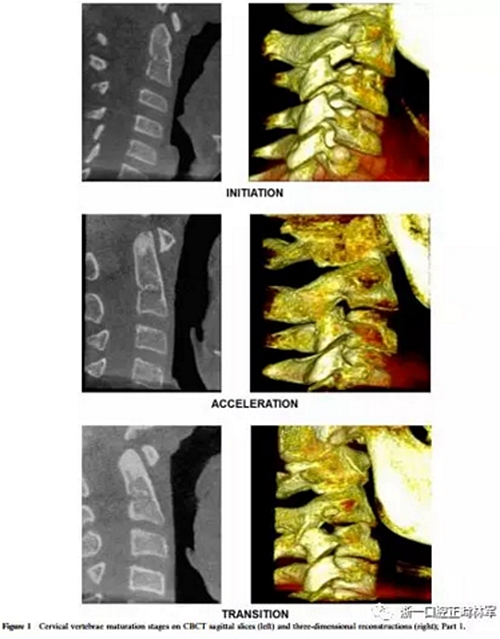

將CBCT三維重建和矢狀切片隨機(jī)分組,并使用軟件OsiriX®(The Osirix Foundation,Geneva,Switzerland)評(píng)估兩次。這些圖像在MacBook Pro(Apple Computer Inc.,Cupertino, CA)。使用OsiriX軟件,通過(guò)使用三維成像技術(shù),從醫(yī)學(xué)文件中的數(shù)字成像和通信獲得三維圖像重建。通過(guò)多平面重組獲得的矢狀切面是通過(guò)將光標(biāo)定位在沿中腭縫線和前鼻棘中心的線上來(lái)選擇的。為了避免視疲勞,每天只評(píng)估20幅圖像。評(píng)估分階段進(jìn)行,每次選擇一種展覽模式,第一次和第二次。CBCT圖像在昏暗的房間里,在具有亮度和對(duì)比度恒定特征的屏幕上進(jìn)行解讀,允許利用軟件的縮放,亮度和對(duì)比度工具來(lái)增強(qiáng)診斷。每個(gè)展覽模式的圖像解讀最短時(shí)間為15天。在第一次評(píng)估后1個(gè)月,考慮到3D重建和矢狀切片(圖1和圖2),讀片員再次讀片,獲取72條記錄。

椎骨C2,C3和C4的分類(lèi)方法分為六個(gè)階段,可以描述如下:

1、初期(頸椎成熟指數(shù)-1)

這對(duì)應(yīng)于青春期生長(zhǎng)噴發(fā)(PGS)的初始階段,其中預(yù)期有80-100%的增長(zhǎng)。椎骨的下邊界是平坦的。在C3和C4的上邊界有一個(gè)從后向前的斜坡。

2、加速期(頸椎成熟指數(shù)-2)

這個(gè)階段接近PGS峰值,預(yù)計(jì)增長(zhǎng)率為65-85%。椎骨C2和C3的下邊界呈現(xiàn)一個(gè)小的凹陷,這在C4上仍然是平坦的。 C3和C4的體部呈矩形。

3、過(guò)渡期(頸椎成熟指數(shù)-3)

這對(duì)應(yīng)于個(gè)人的高峰增長(zhǎng),預(yù)計(jì)增長(zhǎng)25-65%。 C2和C3的邊界呈現(xiàn)出不同的凹陷,這在C4上很微小。椎骨C3和C4的體部是矩形的。